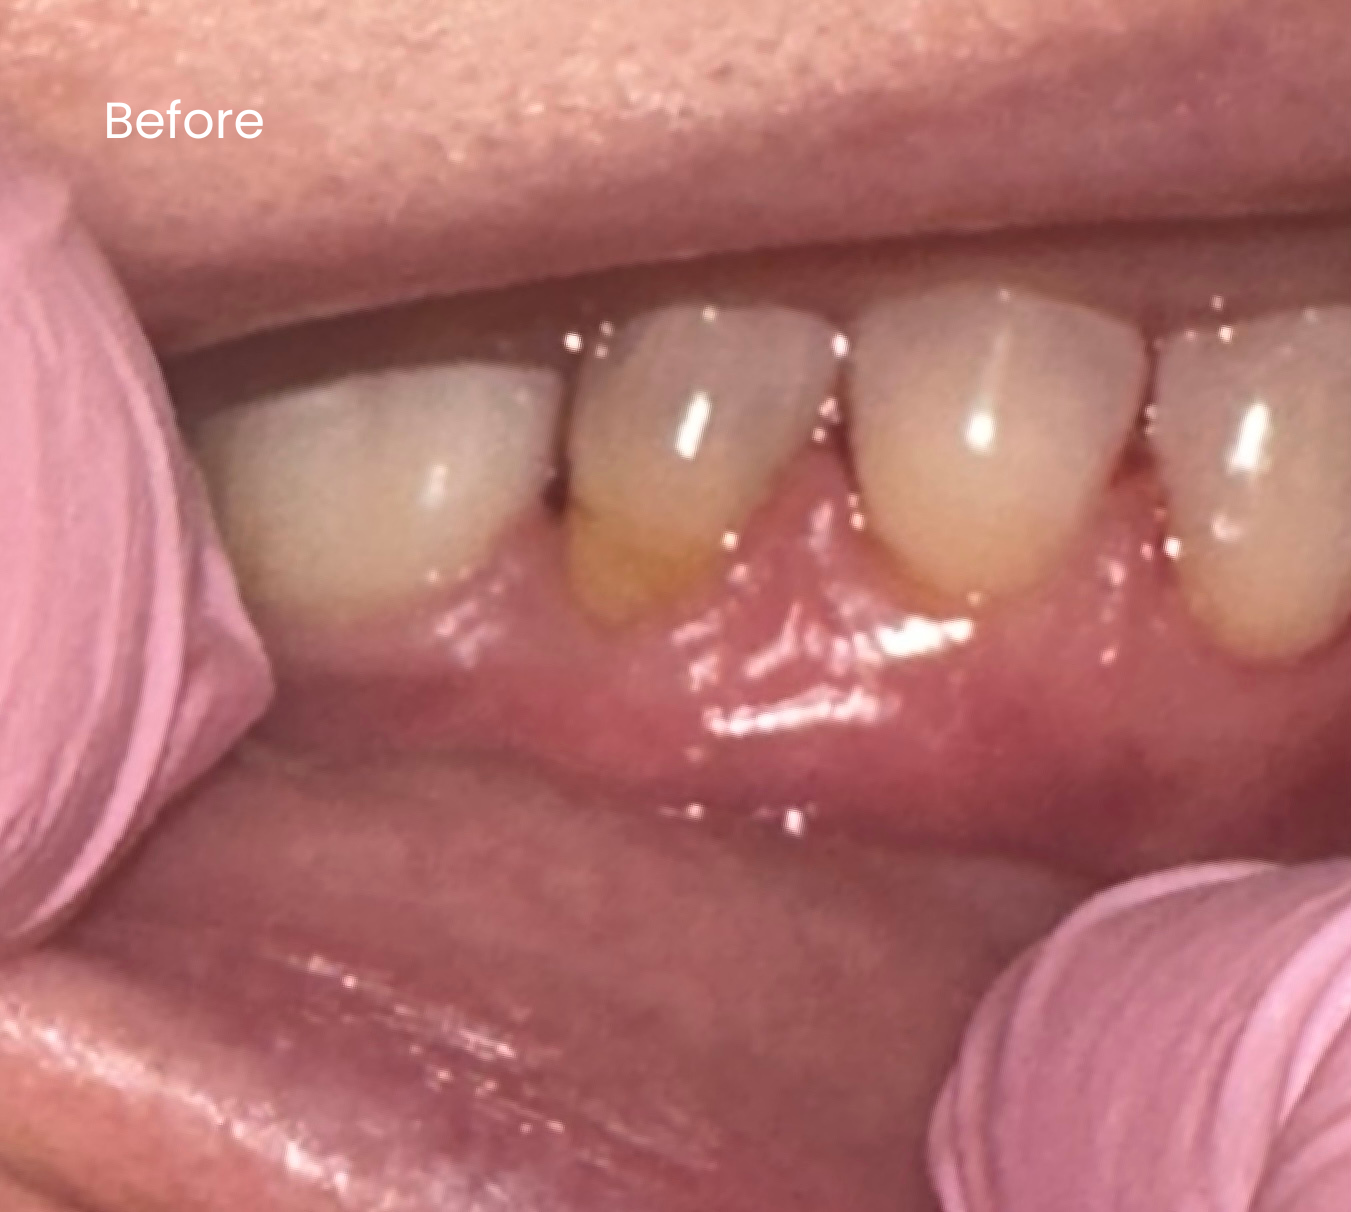

Before & After

Below are examples of the cosmetic outcomes that may be achieved with BPA-free gum coverings. Images are used with full patient consent. Individual results may vary.

Before

After